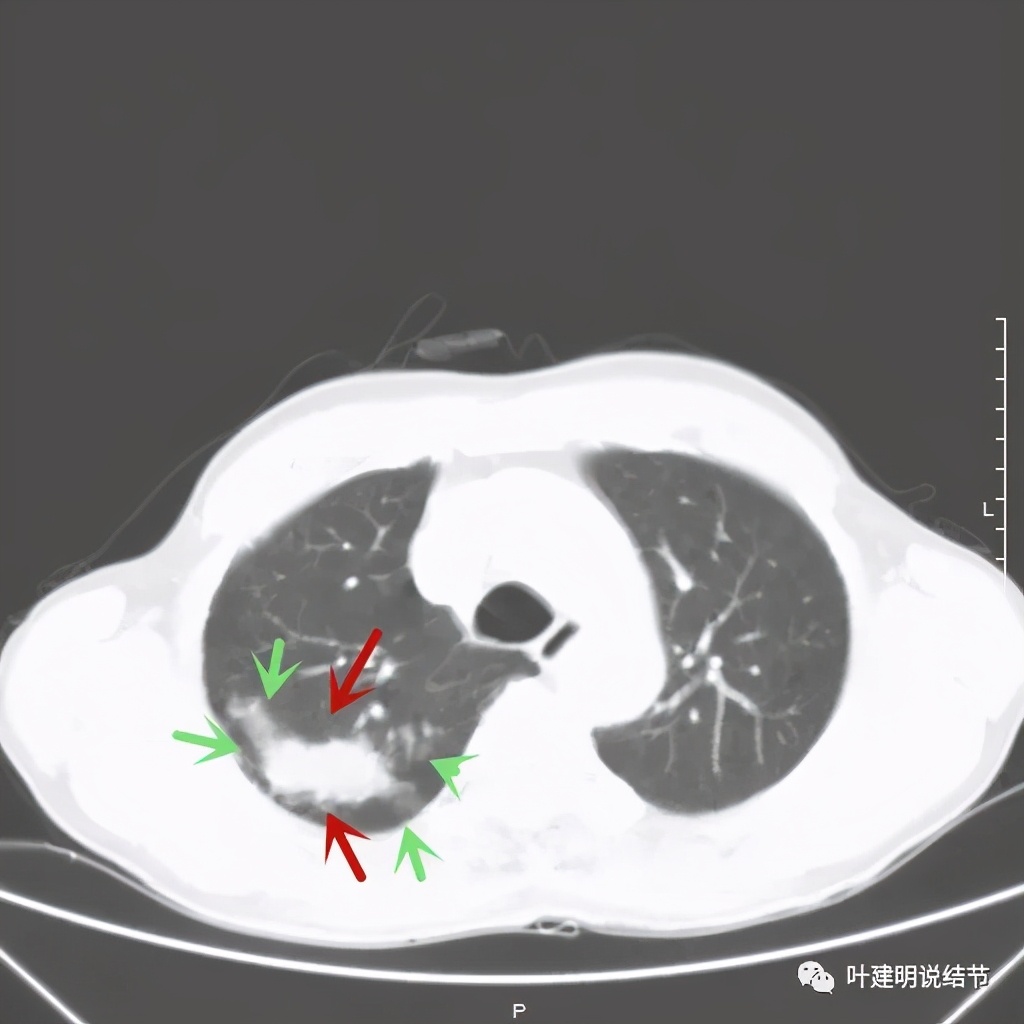

红色示病灶,绿色示病灶旁边有磨玻璃成分,但较为模糊;蓝色箭头示病灶与胸膜间有牵拉,但力度不太够。

总体上感觉,病灶比较大,不规则,不是圆形或圆形生长,周围有模糊磨玻璃影(考虑炎性渗出性?),虽有胸膜牵拉,但力度不够;增强有显著强化。病灶明显却无明显临床症状,普通感染是不像的,要么是结核,要么是肺癌。但肺癌的话,在2年前没有,2年内长到这么大,恶性程度应该很高,但其纵隔淋巴结却没有明显肿大。而且病灶的边缘部分过于光滑,没有见到肿瘤的细毛刺,膨胀性也不够。整体看病灶有点像“腰子”形,弯弯曲曲的。所以我的感觉更倾向结核性。查了肿瘤筛查指标如下: